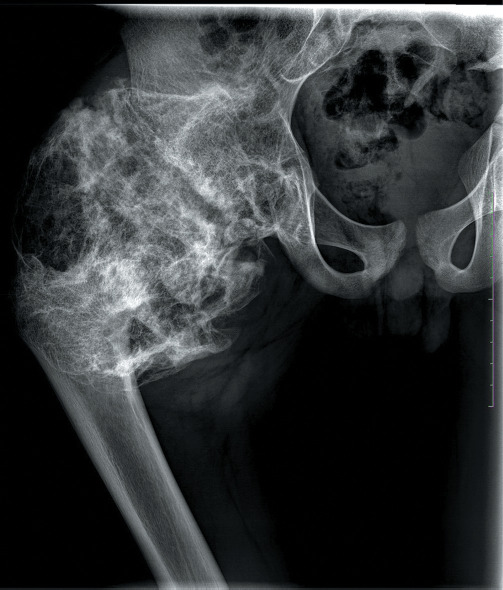

半肢骨骺发育不良(DEH)或Trevor病是一种罕见的非遗传性骨骼发育障碍,影响骨骺和四肢短骨,其特征是骨骺内侧半部分良性过度生长,类似骨软骨瘤。我们在此报告一个非常规的髋关节Trevor病表现,累及整个骨骺。在文献中只发现了少数具有这种不寻常特征的DEH病例。本病例报告的目的是在医生中传播对一例涉及整个股骨干骺的DEH异常病例的认识,该病例已被忽视10年。我们还讨论了疾病发展的自然史、治疗过程中面临的挑战、临床结果和并发症。

Dysplasia epiphysealis hemimelica (DEH) or Trevor's disease is a rare, nonhereditary developmental disorder of skeleton affecting epiphysis and short bones of limbs and characterized by a benign overgrowth of the medial half of the epiphysis resembling osteochondroma. We herein report an unconventional presentation of Trevor's disease of the hip with the involvement of the whole epiphysis. Only a few cases of DEH with such unusual features were found in the literature. The aim of this case report is to spread the awareness among the doctors about an unusual case of DEH with the involvement of the whole capital femoral epiphysis which has been neglected for 10 years. We also discuss the natural history of the development of disease, challenges faced during the course of treatment, clinical results, and complications.